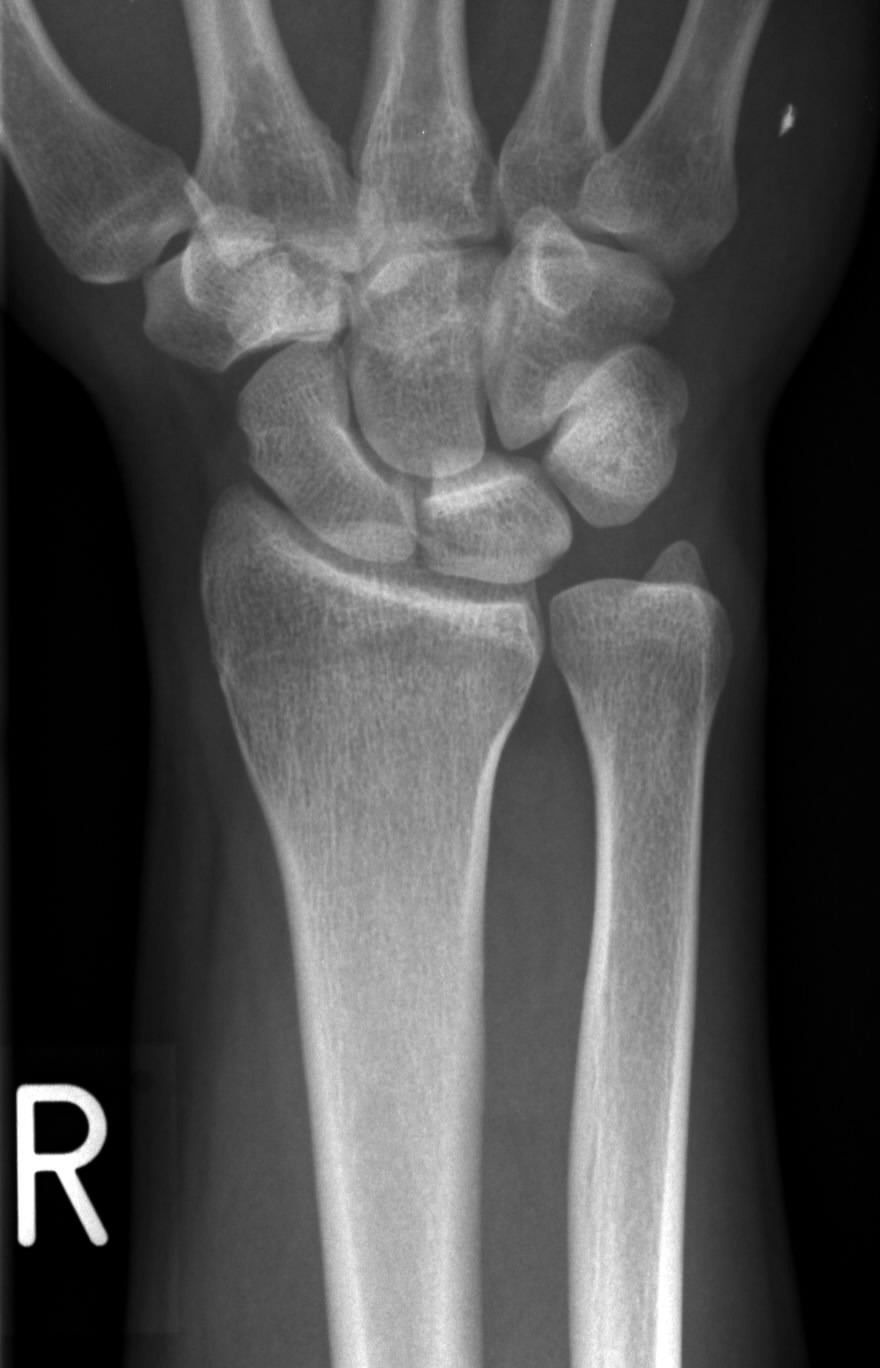

65 Patienten mit 66 in dieser Technik operierten Handgelenken konnten mit einer Mindestnachuntersuchungszeit von 1 Jahr nachkontrolliert werden. Angeborene Ursachen für das Syndrom sind eine Madelungsche Deformität oder in den meisten Fällen eine angeborene Überlänge der Elle die sog. Diagnosis is made radiographically with PA wrist radiographs.

-42 to 23 mm. Positive ulnar variance indicates a longer ulna compared to the radius and a negative ulnar variance indicates a shorter ulna. Fracture-specific proximal ulna plates enable the surgeon to address the specific biomechanical requirements of each fracture pattern.

Maximum forearm pronation results in an increase in positive ulnar variance whereas. Positive ulnar variance is when the ulna extends past the radius 1-4 mm. Mit einem MR.

47 Handgelenke wiesen eine Ulna-neutral-Variante 5 ein Ulna-minus und 14 ein Ulna-plus auf.

The different variance values also signify the distribution of load borne by individual bones ie. In a small percentage of individuals the ulna is longer than the radius. Ulna-plus-Variante von denen der Patienten mit Ulna-minus- bis Ulna-null-Variante im Nachuntersuchungszeitraum unter-scheiden und sich bei Versagen des arthroskopischen Débride ments durch eine zusätzliche UVO annähern 1 35 8 18 21 22. Enjoy the videos and music you love upload original content and share it all with friends family and the world on YouTube. Ein Ulna-Impaktions-Syndrom tritt häufig auf wenn es nach einer Speichenfraktur zu einer Fehlverheilung kommt die eine relative Überlänge der Elle bewirkt. Maximum forearm pronation results in an increase in positive ulnar variance whereas. The most cited value of is 09 mm range. 65 Patienten mit 66 in dieser Technik operierten Handgelenken konnten mit einer Mindestnachuntersuchungszeit von 1 Jahr nachkontrolliert werden. Zwei Ärzte erzählten mir aber das eindeutig eine Ulna Plus Variante zu sehen ist und ich wahrscheinlich Operieren muss da meine Elle 4-5 mm zu lang ist.